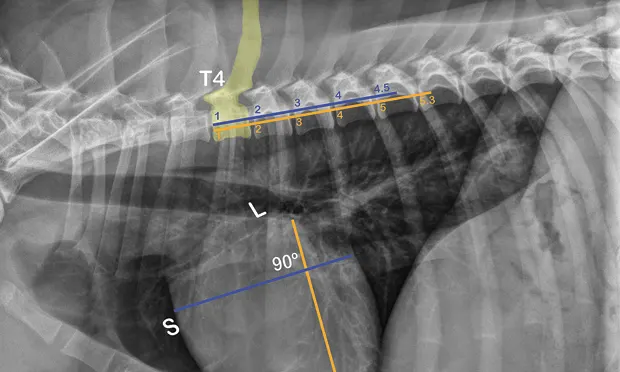

This cardiologist guides you through calculating a vertebral heart scale, its uses, and interpreting findings.